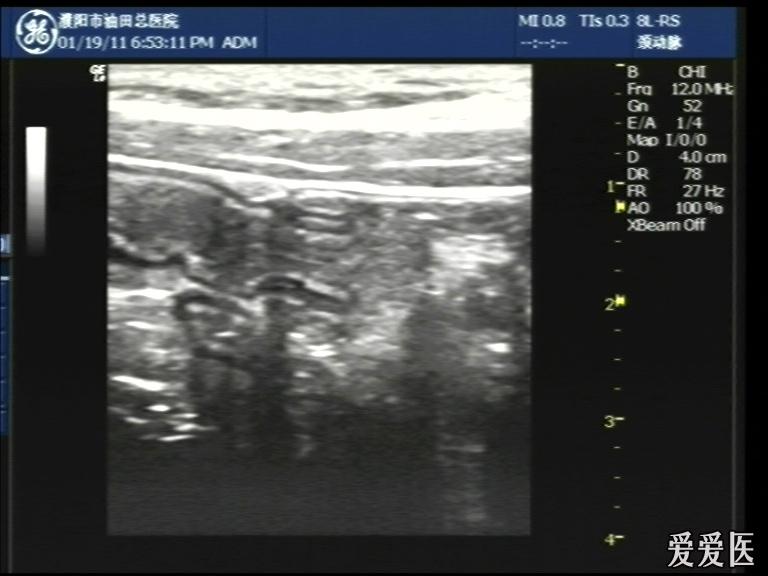

超声检查:于下腹部可见“双环征象”,双环重叠长约6mm,检查期间观察可见肠蠕动;CDFI:未见明显异常血流信号。

超声提示:下腹部双环征,考虑肠套叠可能,请结合临床

“套筒征”、“同心圆征”,很清晰,很经典!

好图,同心圆征。清晰